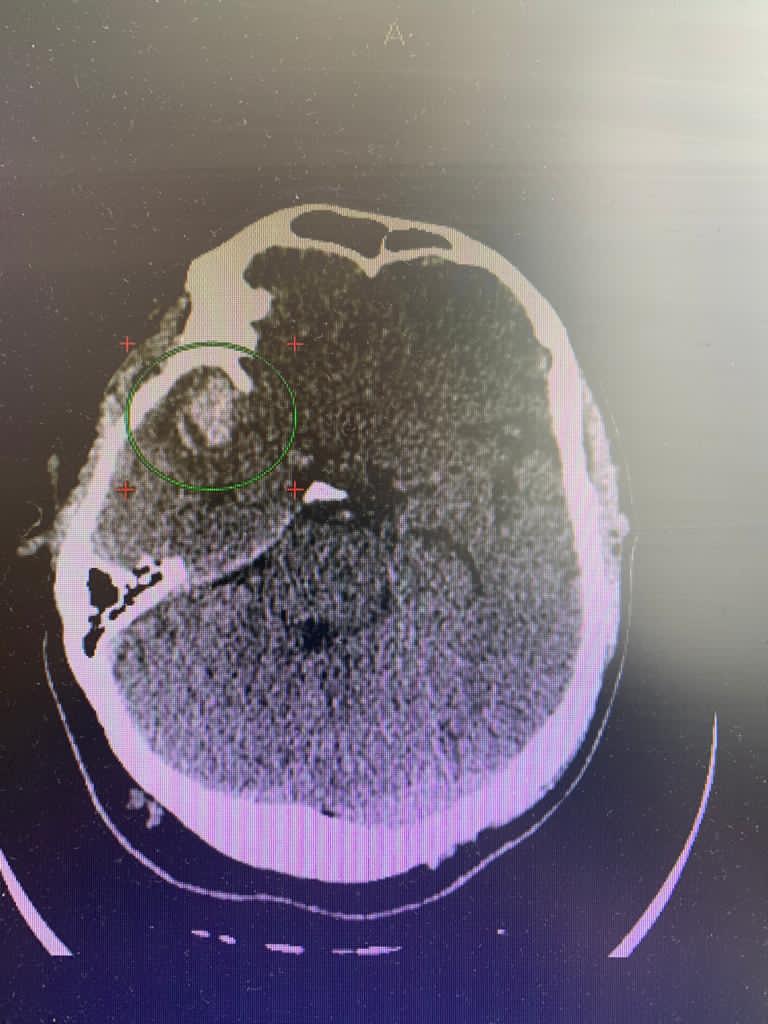

После проведённого обследования был поставлен диагноз: разорвавшаяся мешотчатая аневризма средней мозговой артерии. Опасностью при этом заболевании является высокий риск повторного кровоизлияния, что может привести к летальному исходу.

Послеоперационный контроль- аневризма выключена из кровотока полностью, все сосуды проходимы.